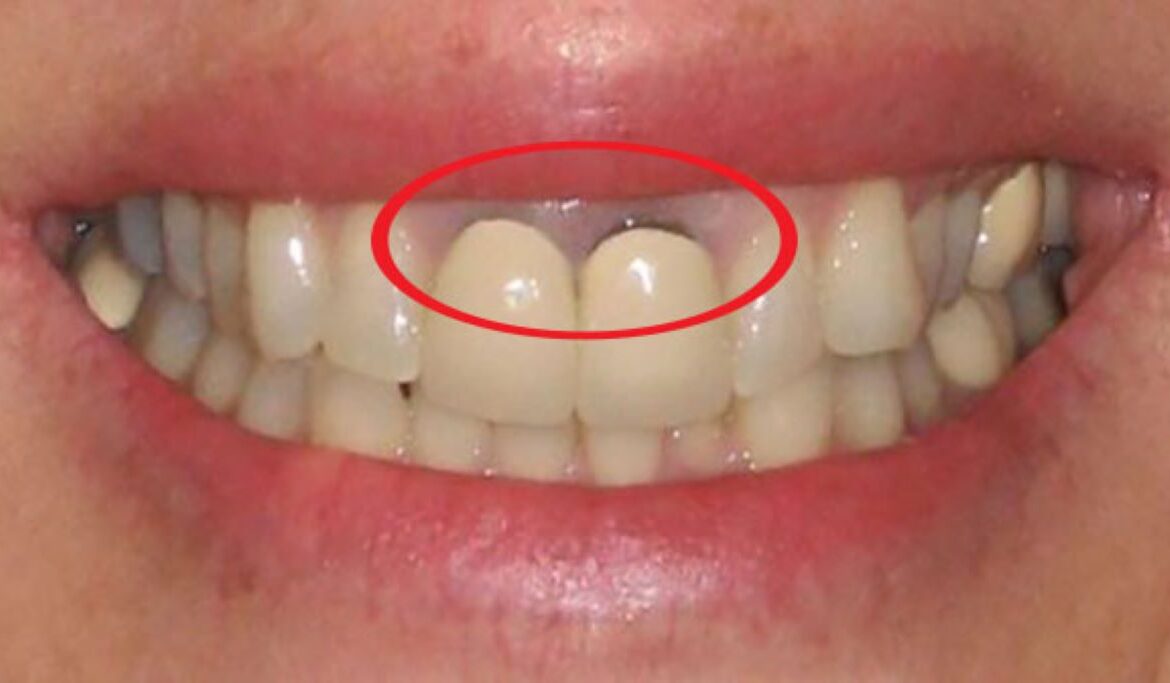

Khi quyết định làm cầu răng sứ, bệnh nhân có thể kỳ vọng vào thời gian phục hình rất nhanh, thường chỉ từ 2 đến 5 ngày. Điều này giúp tiết kiệm thời gian cho bệnh nhân, nhất là những người có lối sống bận rộn. Chi phí cho phương pháp này cũng đề xuất là thấp hơn so với các phương pháp phục hình khác như cấy ghép implant, giúp nhiều người có khả năng tiếp cận dịch vụ nha khoa.

Bên cạnh đó, cầu răng sứ không chỉ khôi phục lại chức năng ăn nhai mà còn cải thiện thẩm mỹ một cách rõ rệt. Cầu răng sứ được thiết kế với màu sắc và hình dạng giống như răng thật, giúp người bệnh tự tin hơn khi giao tiếp.